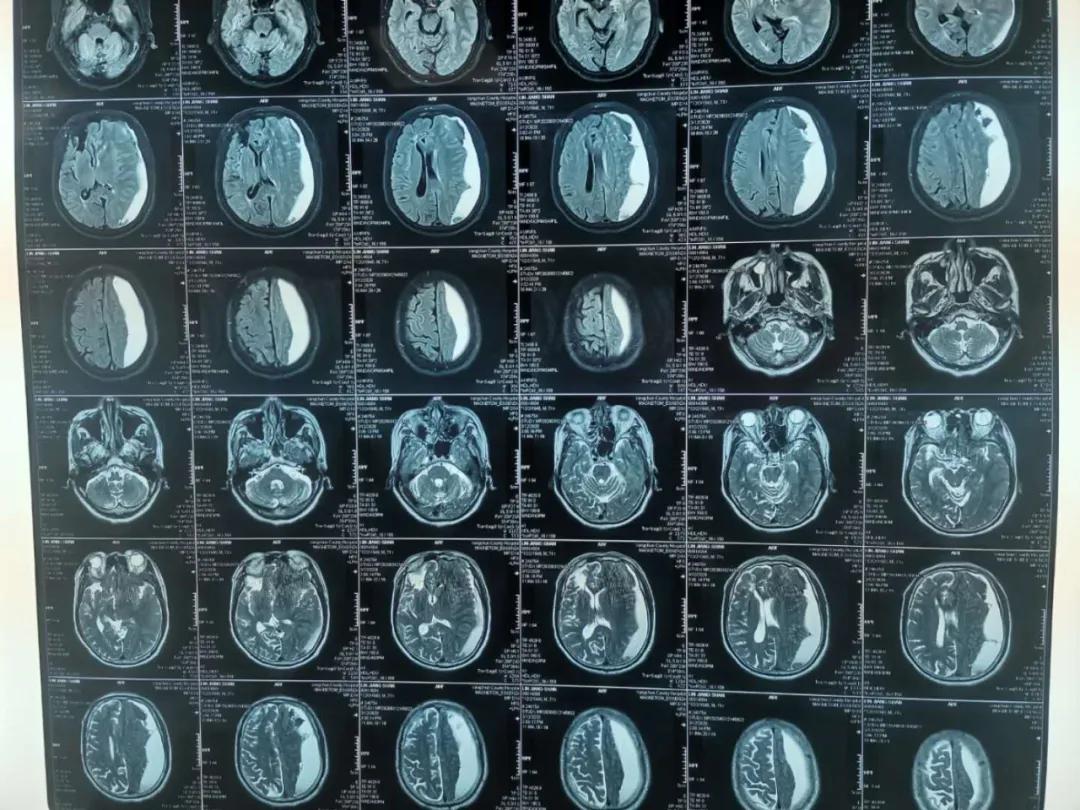

患者林某,男性,82岁,反复头晕半个月,症状时好时坏,未引起重视,未进行治疗,4月27日突发右侧肢体无力,无不能言语,无人事不省,无口吐白沫、双眼上吊、四肢抽搐,无大、小便*禁失**。经查,该患者左侧额、颞、顶部亚急性硬膜下血肿,右侧顶部硬膜下少量出血未除。左侧额颞顶部硬膜下血肿清除术后,于2020.04.28在全身麻醉下行“内镜下颅内血肿清除术+脑积液漏修补术+颅骨修补术”。

术后降低颅内压及抗感染治疗,患者态势良好,病情得到恢复。

术前

术后